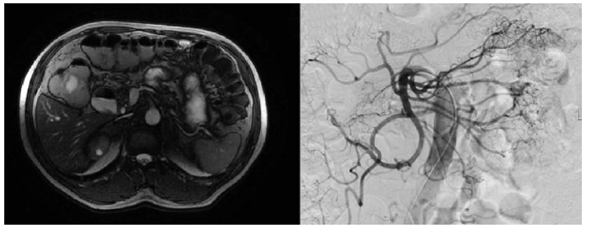

En la arteriografía mesentérica del tronco celiaco y de la aorta, no se observó evidencia de sangrado activo. Por lo anterior, se solicitó una enteroresonancia que fue informada como normal (figura 1).

Para continuar con el estudio, se usó una cápsula endoscópica para buscar sangrado oculto manifiesto, la cual demostró una probable lesión en la segunda porción del duodeno (figura 2). Por esta razón, se practicó una tercera endoscopia de vías digestivas altas que evidenció un divertículo duodenal y una duplicación duodenal tubular, sin alteraciones de la mucosa (figura 3). En las vías digestivas altas se evidenció una duplicación tubular del duodeno en su tercera porción (figura 4).